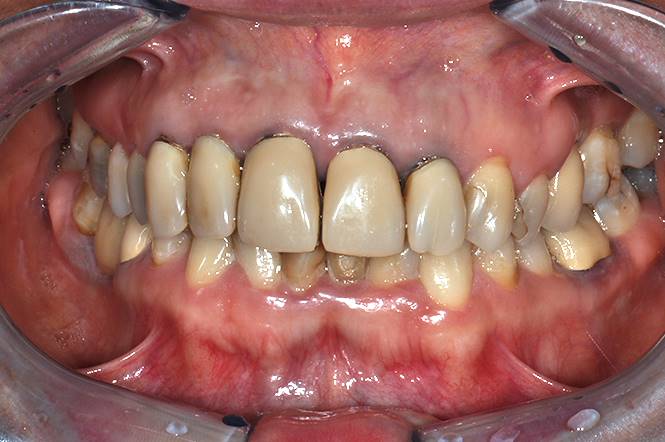

Paziente 46 anni,  è arrivata presso il centro per rivedere i denti superiori perché esteticamente non soddisfacenti.

Dopo attenta analisi abbiamo fatto notare alla paziente che anche il disallineamento, il colore e la forma dei denti inferiori contribuivano a peggiorarne l’estetica, soprattutto durante l’eloquio.